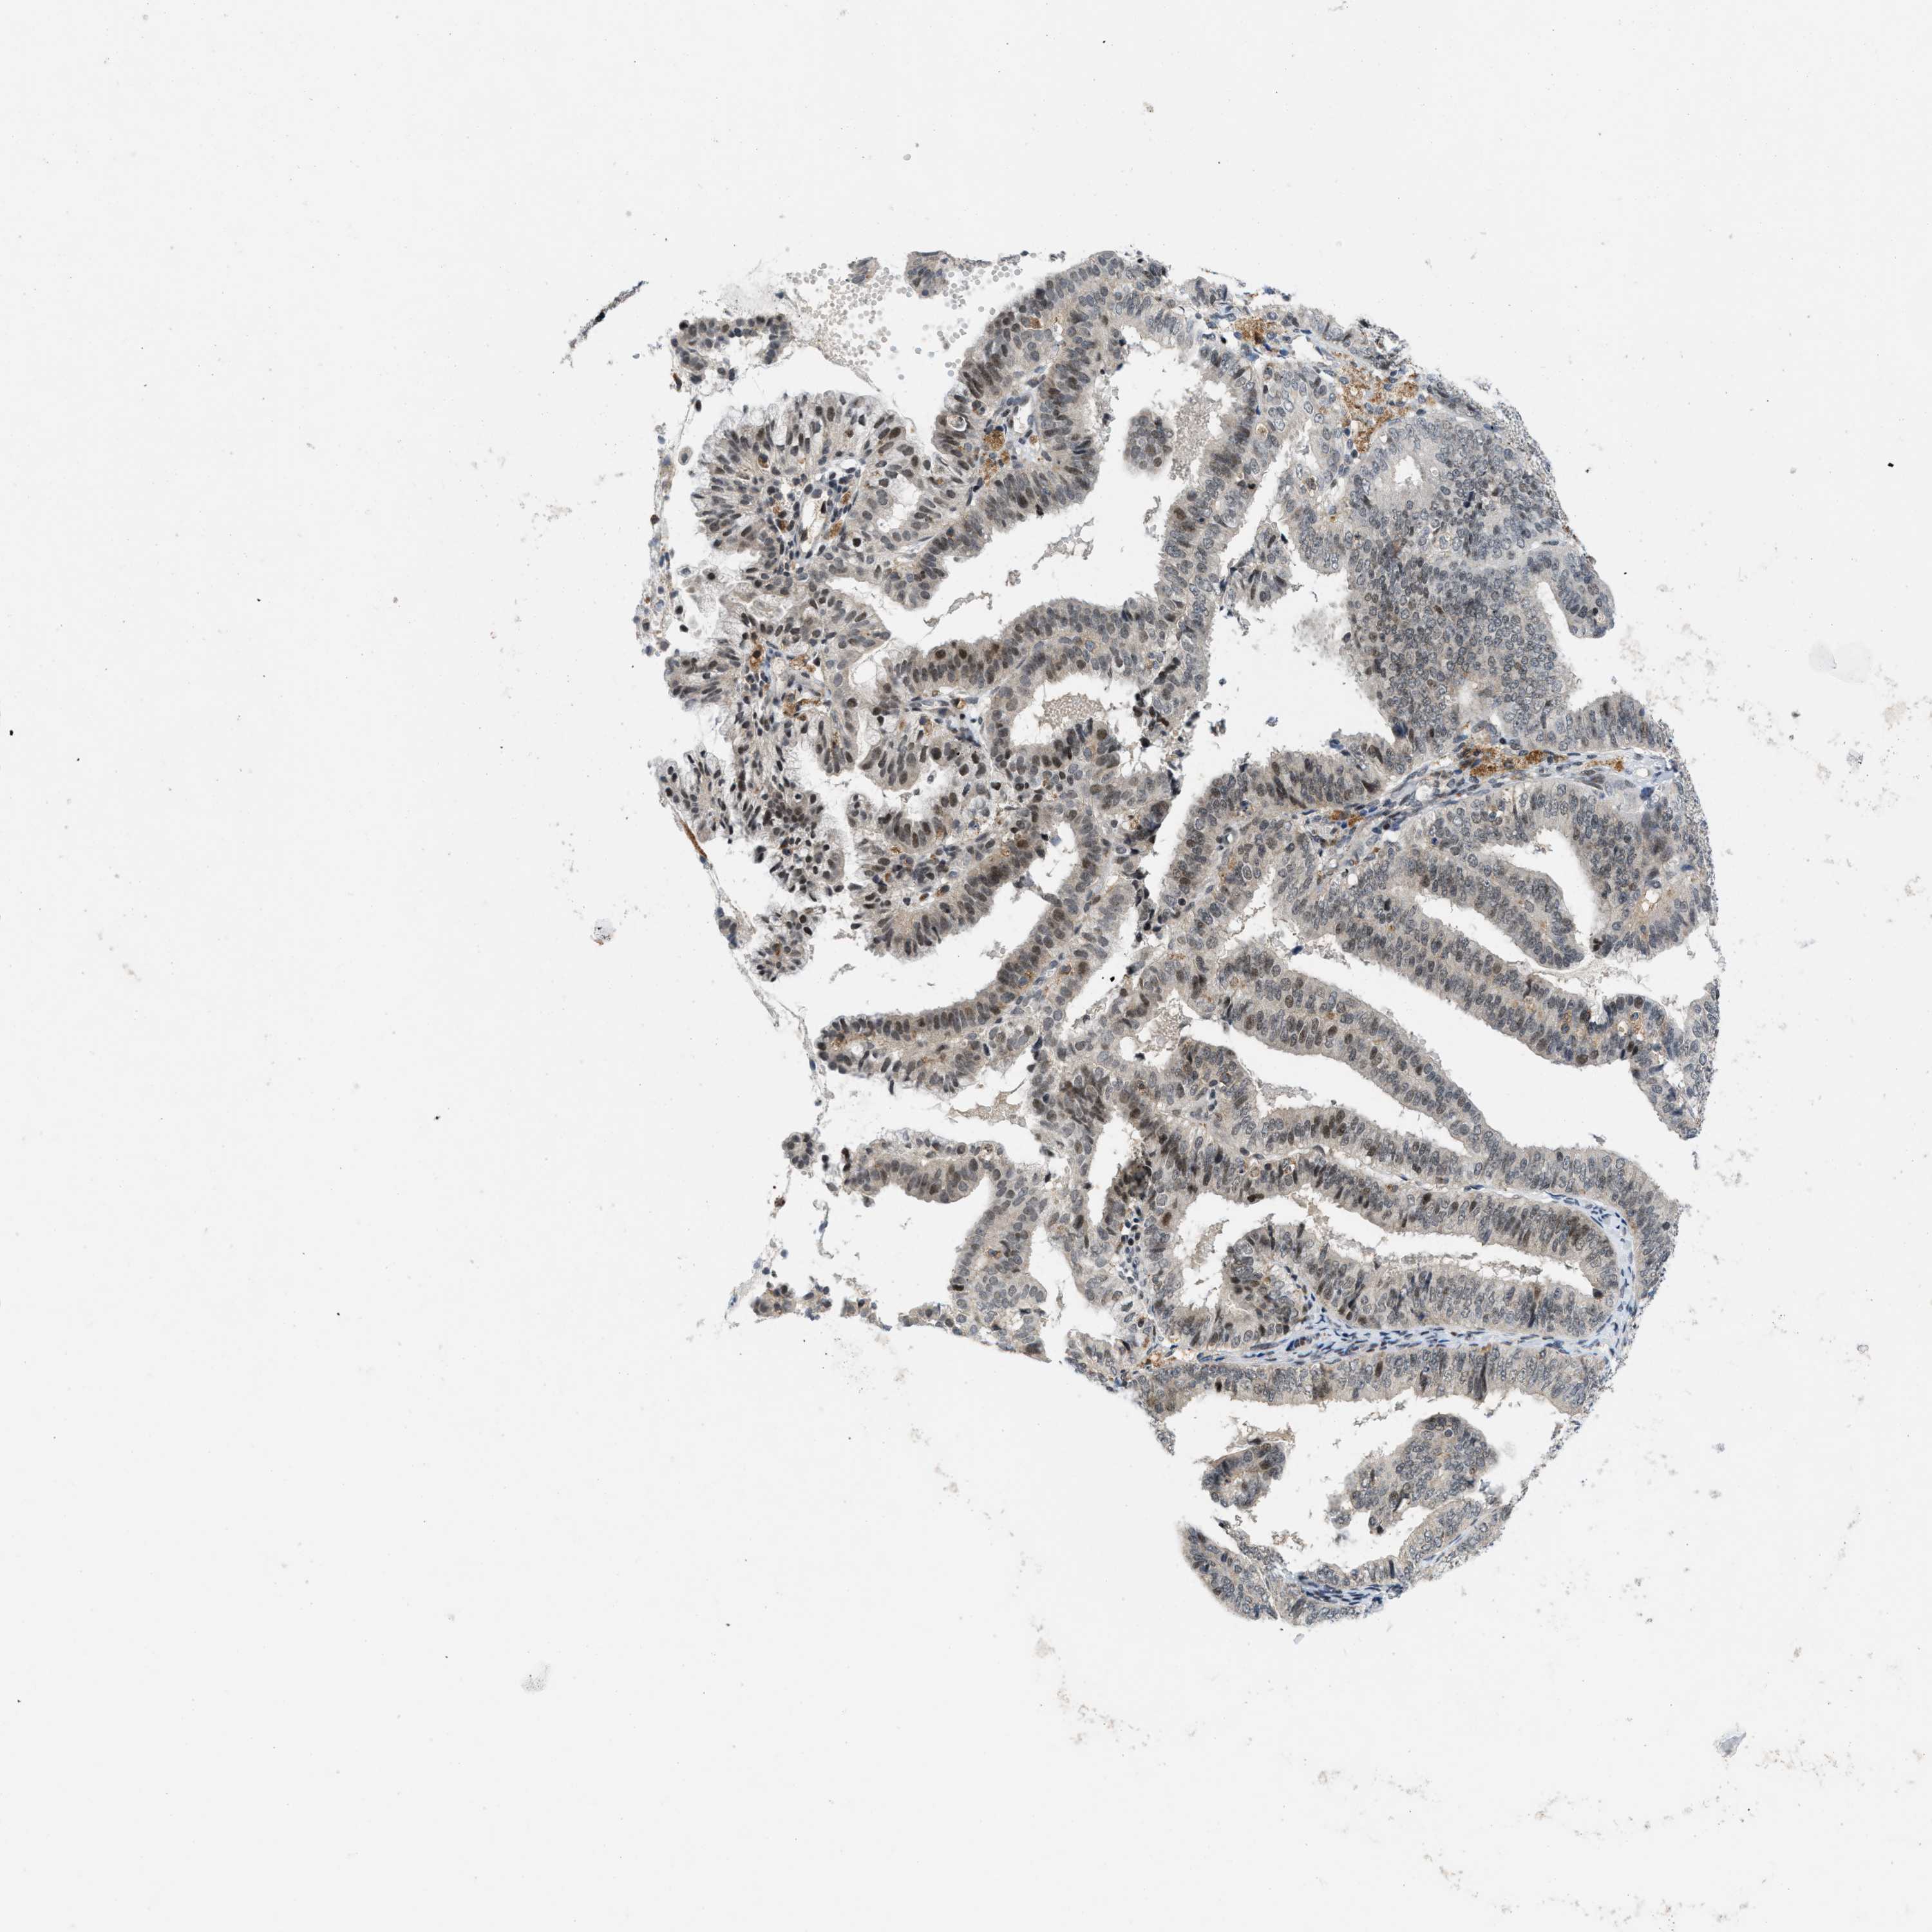

ENDOMETRIAL CANCER - Protein expressioni

A mouse-over function shows sample information and annotation data. Click on an image to view it in a full screen mode. Samples can be filtered based on level of antibody staining by selecting one or several of the following categories: high, medium, low and not detected. The assay and annotation is described here.

Note that samples used for immunohistochemistry by the Human Protein Atlas do not correspond to samples in the TCGA dataset.

Antibody stainingi

Antibody staining in the annotated cell types in the current human tissue is reported as not detected, low, medium, or high, based on conventional immunohistochemistry profiling in selected tissues. This score is based on the combination of the staining intensity and fraction of stained cells.

Each image is clickable and will lead to virtual microscopy that enables deeper exploration of all samples and also displays staining intensity scores, fraction scores and subcellular localization as well as patient and tissue information for each sample.

Antibody CAB016136

Antibody CAB017773

Staining

High

Medium

Low

Not detected

Intensity

Strong

Moderate

Weak

Negative

Quantity

>75%

75%-25%

<25%

None

Location

Nuclear

Cytoplasmic/membranous

Cytoplasmic/membranous,nuclear

Adenocarcinoma, NOS